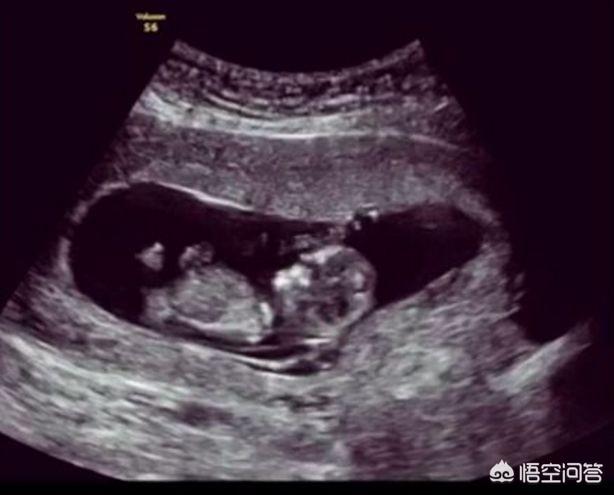

1.胎嚢の状態

これは妊娠初期にのみ見られる。胎嚢の直径は妊娠初期で2cm、妊娠後期で5cmに達することがあるが、これは正常と考えられている。

胎嚢の位置は子宮底部、子宮前壁、子宮後壁、子宮上部、子宮中央部のいずれも正常と考えられる。形態は円形、楕円形、透明で、正常と考えられる。

胎嚢の形が不規則で、ぼんやりしていて、低い位置にあり、母親が腹痛や膣からの出血を経験した場合、流産の可能性が非常に高いことを認識しておくことが重要です。

2.胎児の頭部の状態

外形が完全であれば正常、欠損や奇形があれば異常、脳の正中線にずれがなく、水頭症がなければ正常である。平均的な満期産児の場合、両頭頂の直径は9.3cm以上になります。